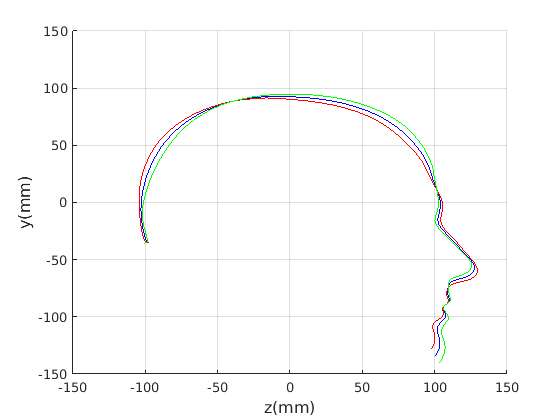

To emphasise the form/shape variation for each of these cases, the mean shape and shapes at mean for the four most significant modes of shape variation are plotted in Fig. 19 and Fig. 20. In this case, ECN normalisation is used.

For the cranial sagittal profile model, when not scale-normalised (Fig. 20, left column), the following dominant shape modes are observed:

-

1.

Cranial height variation with a low correlation with cranial length.

-

2.

Cranial length variation with a low correlation with cranial height.

-

3.

A cranial bulge that varies between the front and rear of the cranium.

-

4.

This mode picks up minor variations on cranial shape and some noise where hair exits from the latex cap.

When data is scale normalised (Fig. 20, right column), cranial height and length are more significantly correlated, as shown in the first mode (top right in figure). The second mode model a bulge that can vary from the front to the rear of the cranium. Taken together, these two modes capture close to 90% of the variation in the training set. A two-dimensional model, based on these two modes is used in a clinical case study in Sect. 8.